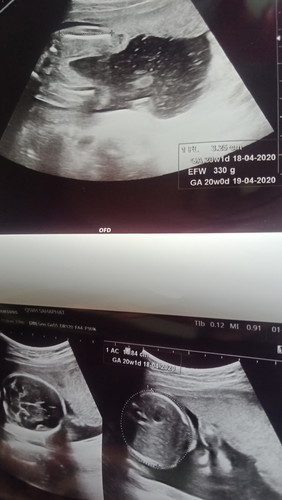

ตั้งครรภ์

แม่ๆช่วยดูหน่อยได้ไหมค่ะว่าน้องเป็น. ญ / ช

อยากรู้เหมือนกันค่ะแม่ๆช่วยดูหน่อย5เดือนแล้วแต่ยังไม่รู้เลยจะได้ ญ/ช ค่ะ

น่าจะหญิงนะคะ เพราะระหว่างขาไม่มีอะไรโด่เด่

น่าจะหญิงนะคะ คิดว่าถ้าชายน่าจะมีอะไรโด่ๆมา

น่าจะ ญ นะคะ ขอเรา 20w เห็นมีอะไรๆโผล่ออกมาค่ะ

ญ คะ เหมือนของเราเลย หมอบอกถ้า ช จะมีโผล่ๆ

ญ คะ ของเราก็แบบนี้ไม่มีอะไรโผล่ตรงกลาง

น่าจะหญิงนะคะ เพราะไม่มีแท่งโผล่มาเลย

น่าจะหญิงค่ะ เพราะไม่มีอะไรโผล่มา